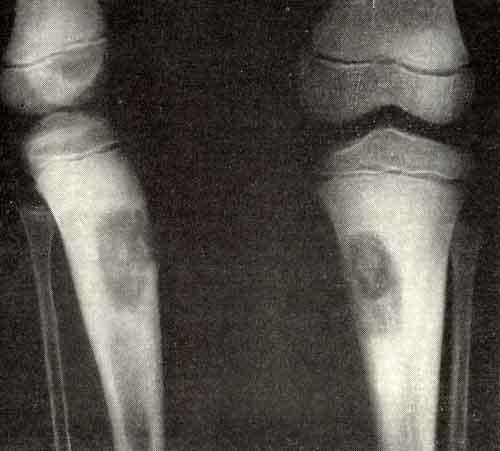

На рентгенограммах выявляется экзофитное образование с четкими фестончатыми очертаниями, которое обычно локализуется в метафизарной зоне и растет в сторону эпифиза. Опухоль представляет собой четко очерченный очаг деструкции, длина которого может колебаться от 1-2 до 6-8 сантиметров. Корковый слой над очагом вздут и истончен. По краю образования выявляется склеротический ободок, в очаге деструкции могут обнаруживаться вкрапления извести и трабекулярный рисунок. Если опухоль расположена субпериостально, кортикальный слой становится неровным. Периостальной реакции обычно нет. При локализации новообразования в области позвонков часто наблюдается прорастание надкостницы.

Обычно локализуется в метафизарной и метаэпифизарной зоне длинных трубчатых костей нижних конечностей. Первое место по распространенности занимает хондромиксоидная фиброма проксимального конца большеберцовой кости. Нередко обнаруживается в метатарзальных костях и пяточной кости. Возможно также поражение ребер, плечевых и тазовых костей, а также позвонков, грудины и костей черепа. 25% от общего числа случаев приходится на поражение плоских костей. Наиболее агрессивным ростом отличается опухоль в области позвоночника.